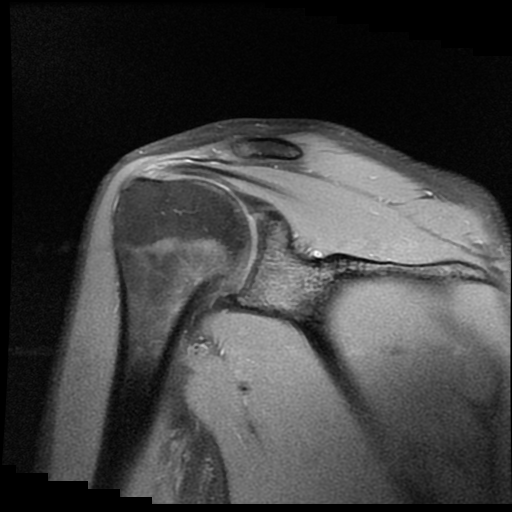

TECNICA EMPLEADA

Se coloca al paciente en decúbito supino, utilizando bobina dedicada de 8 canales, obteniendo imágenes en planos axial, sagital y coronal, secuencias, Spin Echo, Eco de Gradiente, potenciadas a Densidad de Protones, con pulsos de saturación de grasa.

HALLAZGOS IMAGENOLOGICOS

Lesión post traumática de Hill Sachs a nivel de la cabeza humeral, tendinosis aguda del supra espinoso.

La lesión de Hill-Sachs es un defecto de impactación en la región posterosuperolateral de la cabeza humeral, secundario a luxación o subluxación anterior del hombro. Se produce cuando la cabeza humeral, desplazada anteroinferiormente, colisiona y se “muerde” contra el borde anteroinferior de la glenoides.